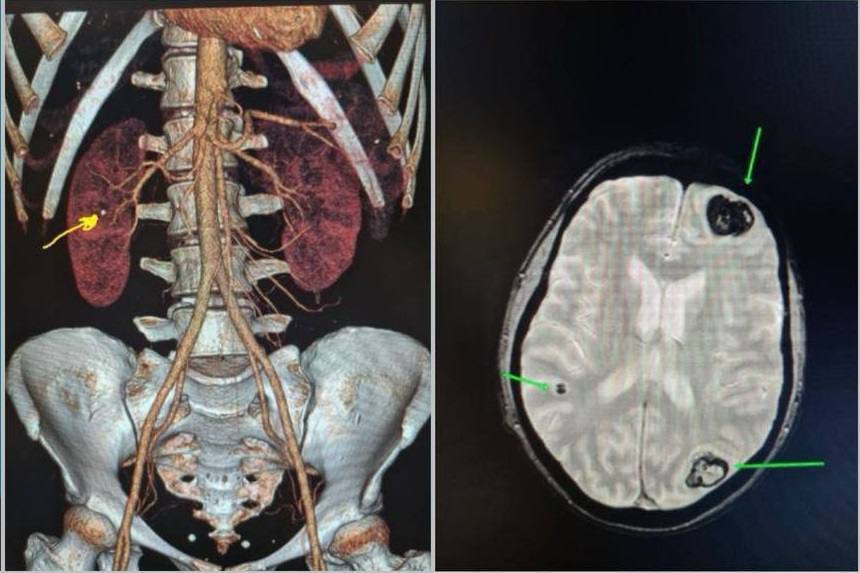

Второе мнение пэт

Второе мнение пэт 110 фото